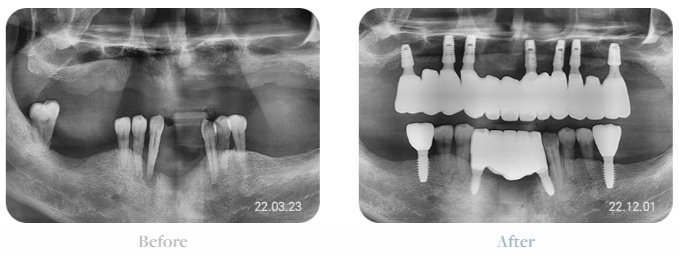

전체임플란트후기 비용

전체임플란트는

사진에서 확인할 수 있듯이

최소 식립으로 비용을 절약할 수 있습니다.

만약 빠진 치아 공간을 모두

임플란트 식립을 한다면

부작용 확률을 높이고

안정성이 떨어지며

비용의 부담이 높게 됩니다.

최소 식립 전체임플란트는

기능성 회복에 반드시 필요한 위치만 파악해

세밀하게 저작력 분산을 계산,

환자의 전체적인 여건 등을 고려하여

치료 계획을 세워야만 합니다.